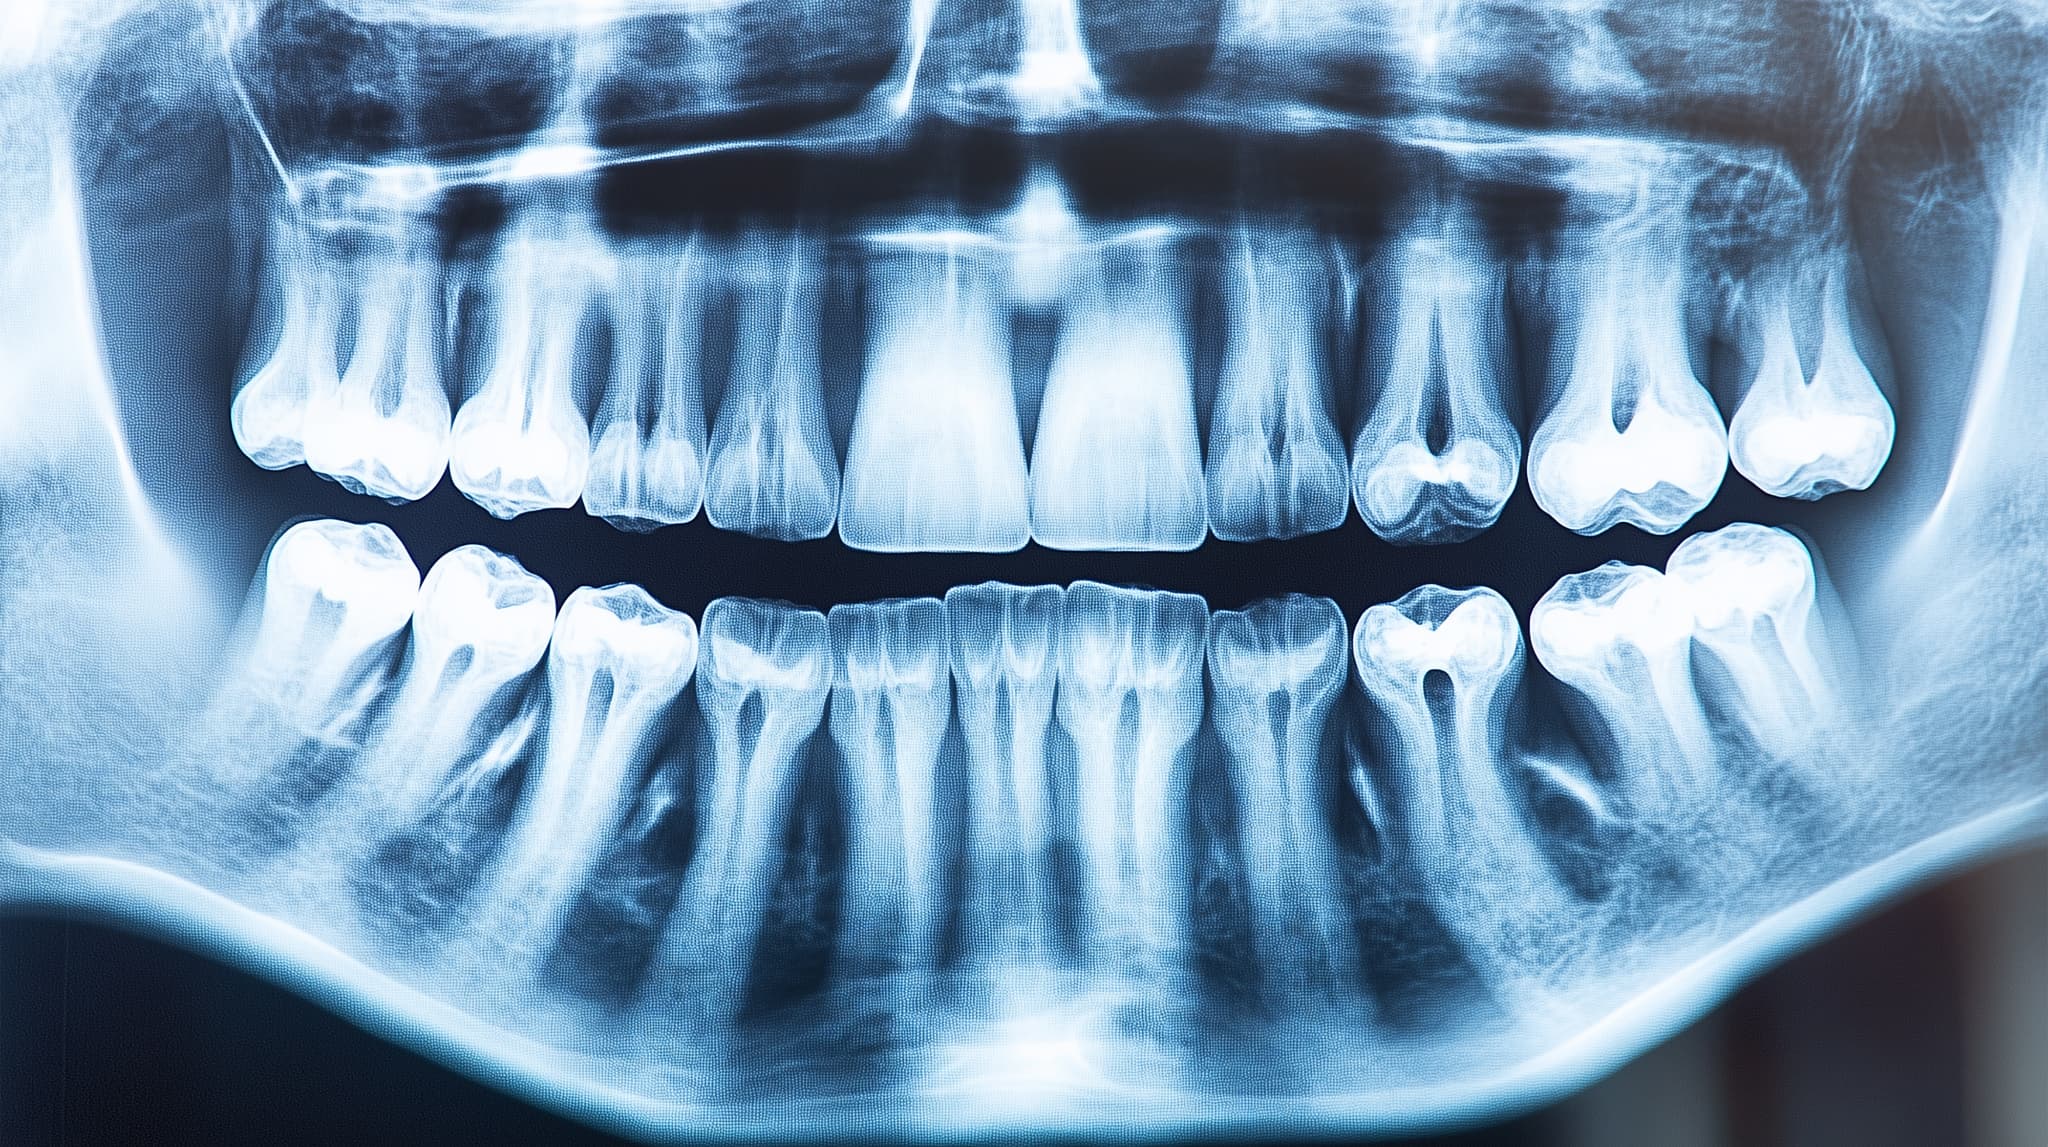

精密検査

治療を開始する前には精密検査を行います。精密検査では、歯型の採取やレントゲン撮影、顔の写真の撮影などを行います。検査結果をもとに、一人ひとりに合わせた治療計画が立てられます。